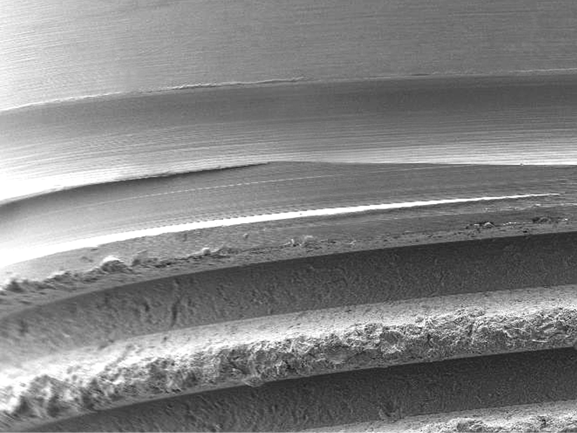

Resorbable Blast Media

Proven resorbably blast media (RBM) surface with proprietary processing to promote osseointegration